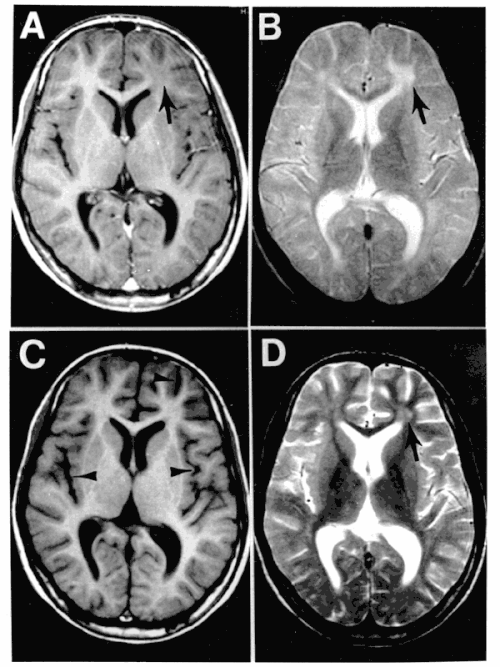

아급성 경화성 전뇌염 (SSPE, subacute sclerosing panencephalitis)이라하여, 홍역을 앓은 후 회복된 후에

수년이 지나 평균 12년 후에 소아 후기~젊은 성인에서 발생하는 만성 뇌염입니다.